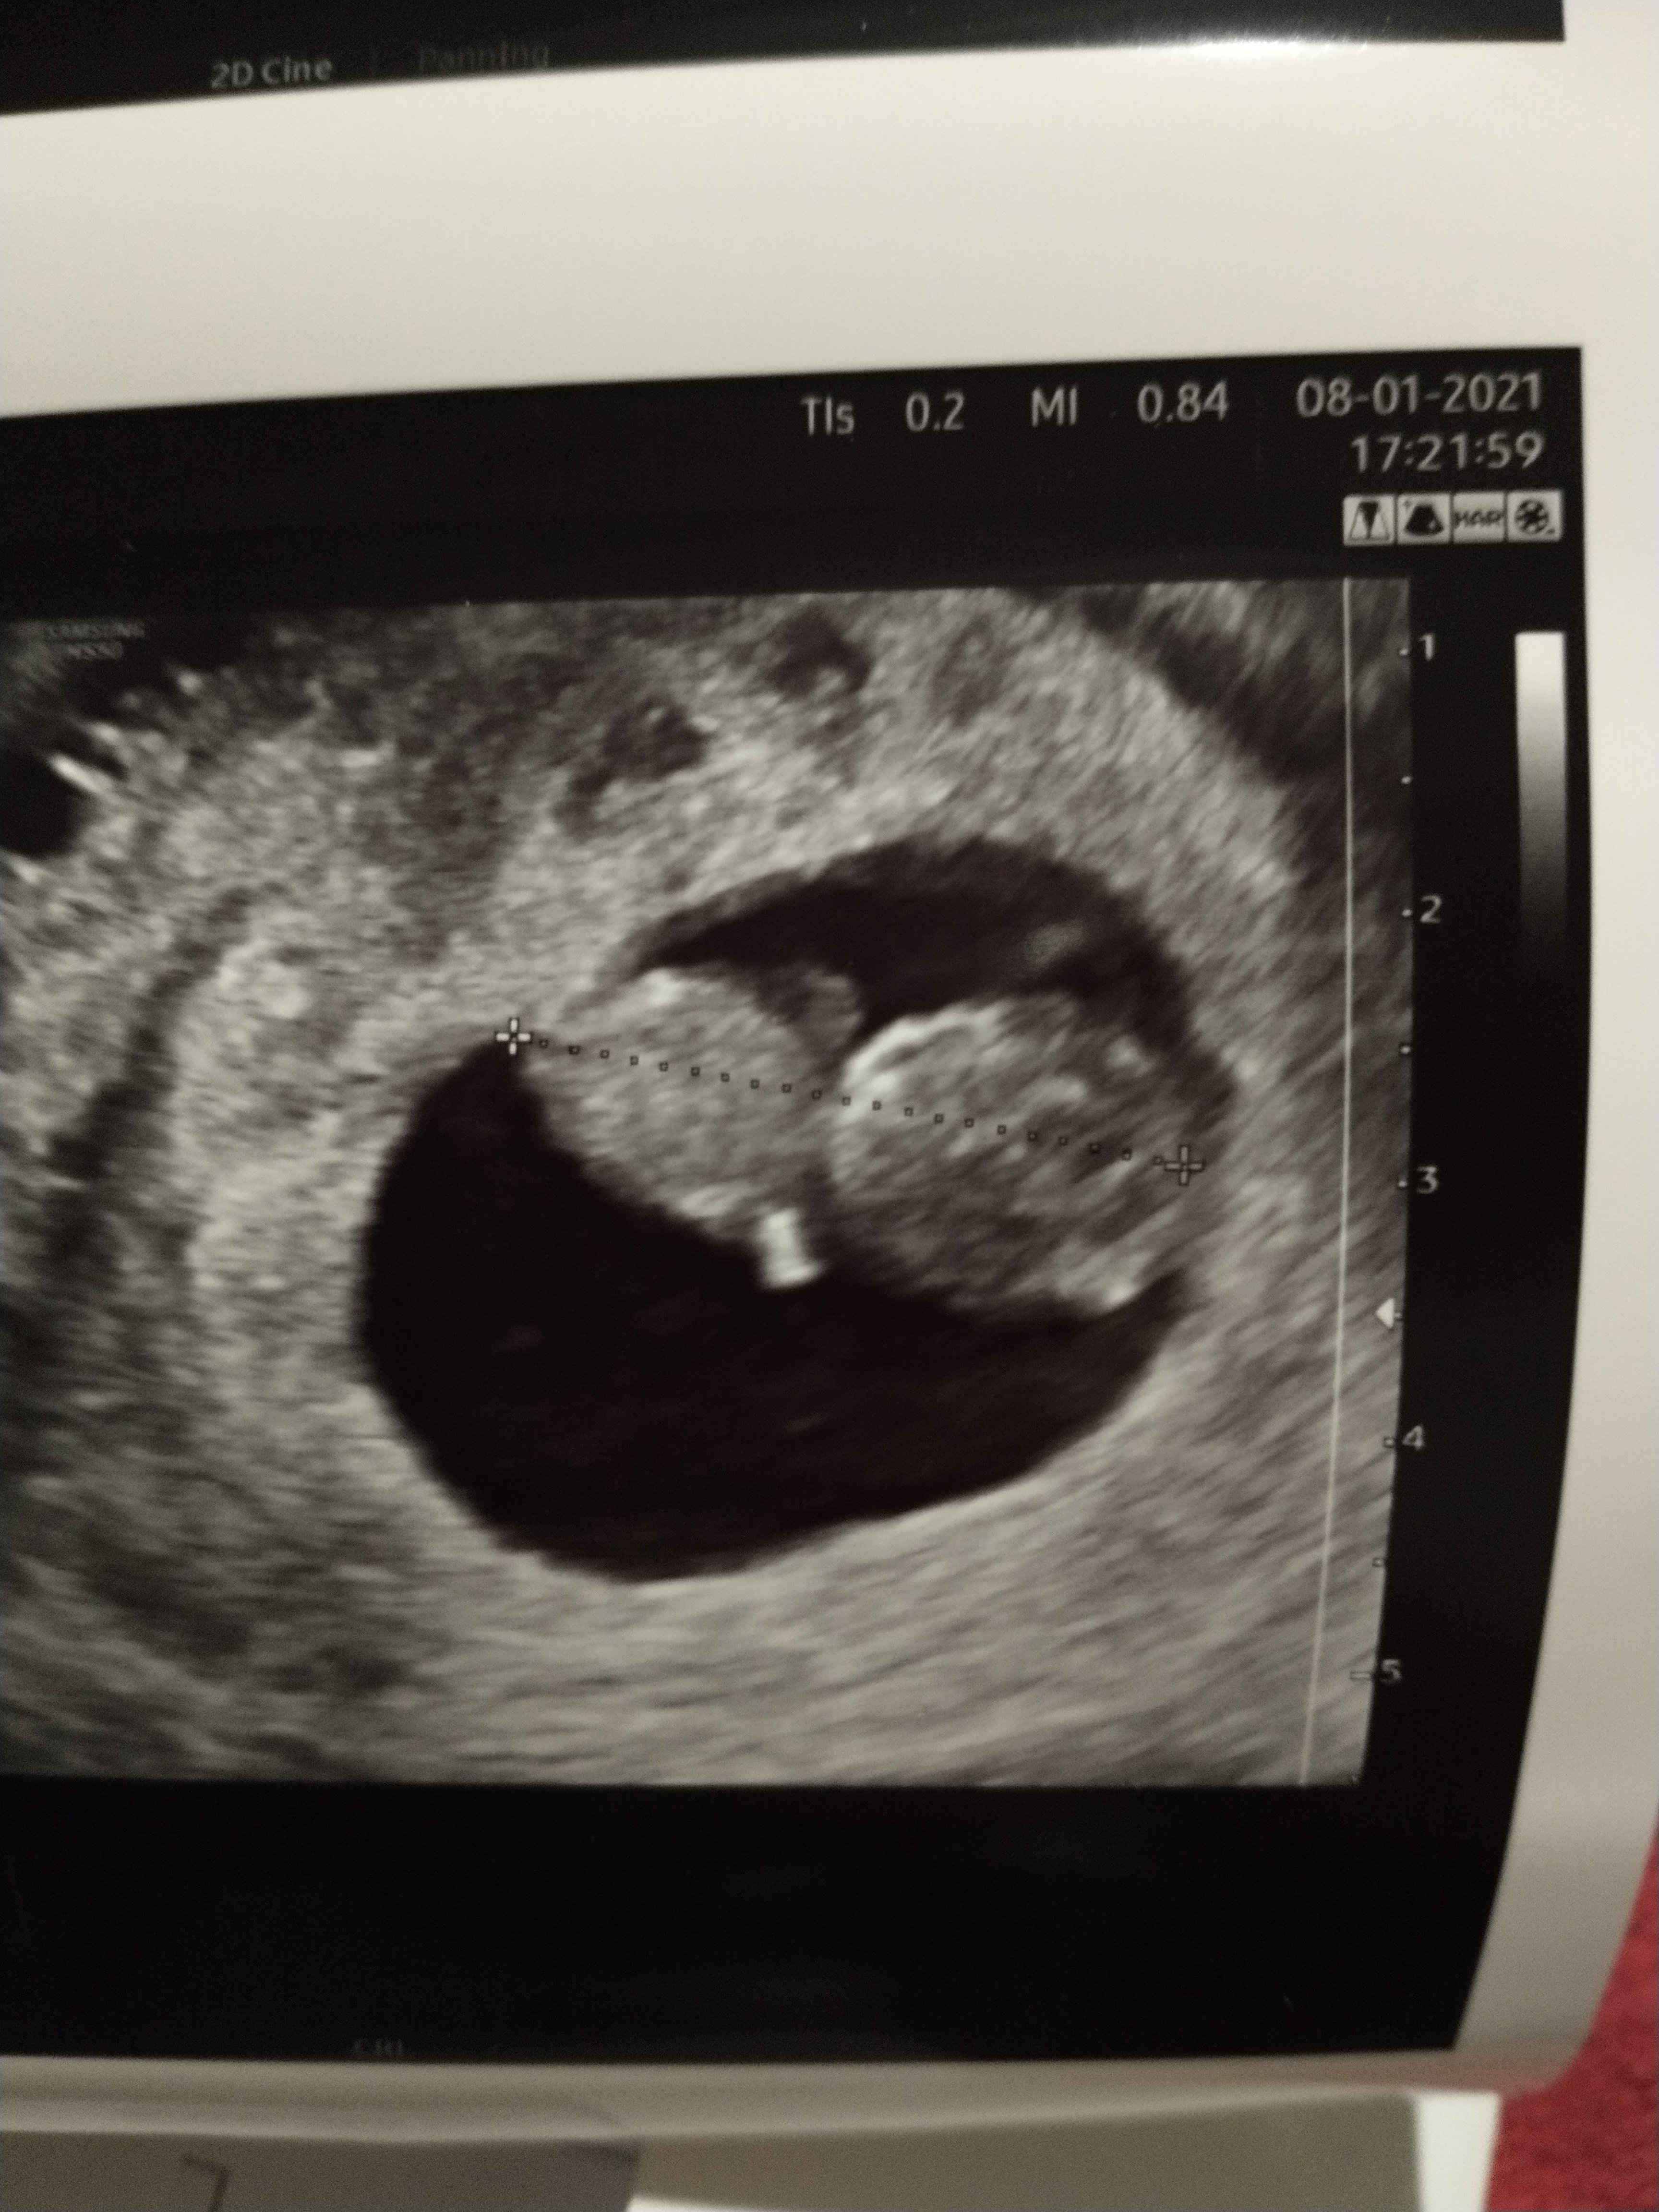

Melduje się po wizycie, uspokojona i zakochana 🥰 wszystko pięknie się rozwija, w środku czysto, nie ma żadnych zmian. Lekarka pozwoliła na obecność męża, szczęśliwy był bardzo ♥️ na dodatek najpierw on z lekarka oglądali malucha, także ja mogłam obserwować reakcje męża 😍 A jeszcze lepsze uczucie było jak ginekolog obróciła monitor do mnie a maluszek tak się zaczął wiercić, machać "rączkami", coś pięknego 🥰 załączam zdjęcie, jednak nie chciał się ładnie ustawić, na żywo latał jak szalony, wiercipięta😃😃

IMG_20210108_195531641.jpg